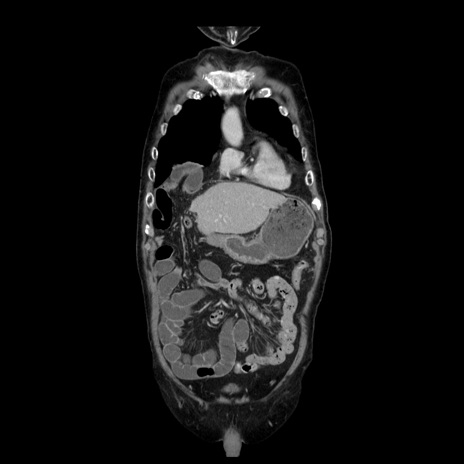

症例21(冠状断像)

【症例】70歳代男性

【主訴】腹痛

【現病歴】肝硬変・肝細胞癌にてかかりつけの方。約9時間前に食後より腹痛出現。症状が徐々に増悪し、嘔吐出現したため来院。

【既往歴】肝硬変、肝細胞癌(RFA、TACE後)

【身体所見】意識清明、表情苦悶様、BT 36℃、BP 129/78mmHg、P 88bpm、SpO2 97%(RA)、右上腹部から心窩部にかけて圧痛あり、反跳痛なし、筋性防御あり。

【データ】WBC 5800、CRP 0.16